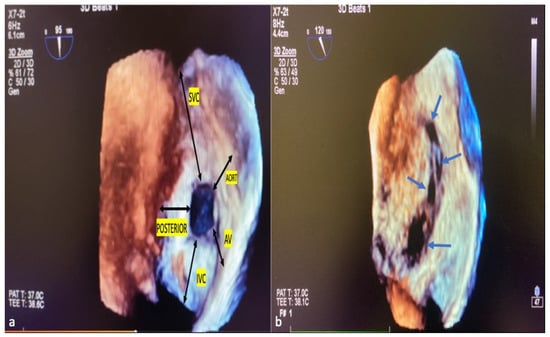

ASD residual rims: This is defined as the distance between the edges of the ASD and the surrounding intact atrial septum tissue. ASD residual rims were examined in detail by slicing or cropping 3D full-volume and 3D zoom datasets. The maximum rim length was based on the value measured at the end of the systole. The superior or inferior residual rim was determined by the distance from the defect edge to the SVC or IVC in the mid-to-high esophageal position. The posterior rim was measured as the distance between the defect edge and the posterior wall. The antero–superior (aortic) residual tissue rim is the distance between the defect edge and the aortic wall in the mid–upper esophagus position in the short axis. The antero–inferior residual rim (AV valve rim) is the distance between the ASD border and the atrioventricular valve annulus in the mid-esophageal 4-chamber view. ASD morphology: From the en-face view, when the minimum diameter was equal to or greater than 75% of the maximum diameter, it was considered a circular defect, and when it was smaller, it was considered an elliptical or oval defect [21]. Complex ASDs were defined according to their shape and/or location. The ASDs are considered complex if the defects are large (>26 mm), have deficient septal rims (particularly inferior rim), atrial septal aneurysm is present, or defects are multiple or fenestrated [22]. Figure 4a,b show the ASD rims defined, respectively, and a multi-fenestrated ASD example.

Figure 4.

ASD rims and multi-fenestrated ASD image in 3D TEE. The tissue lengths indicated by black arrows in the RA (a), en face view, describe the ASD rims. Example of complex, multi-fenestrated ASD (Blue arrows) (b). SVC, superior vena cava; AV, atrioventricular; IVC, inferior vena cava; POSTERIOR, posterior rim; AORT, aortic rim.